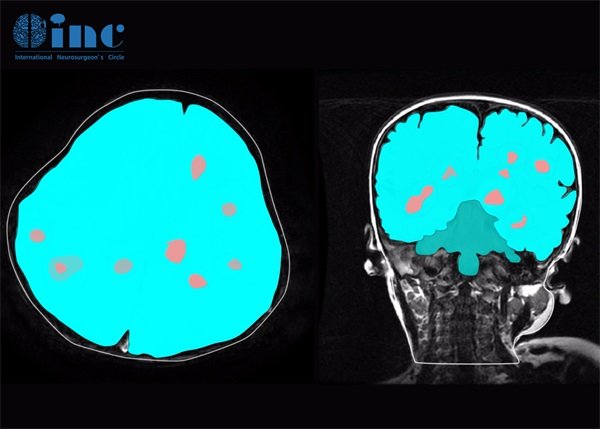

海绵状血管瘤在CT中的表现

海绵状血管瘤在CT影像上一般呈现为低密度或等密度的病灶。经过对比增强扫描后,肿瘤的轮廓通常会更清晰,并且可能显示出“蜜蜂窝”状的特征。这使得海绵状血管瘤在影像学上具有较高的可识别性,尤其是在专业医生的判断下。